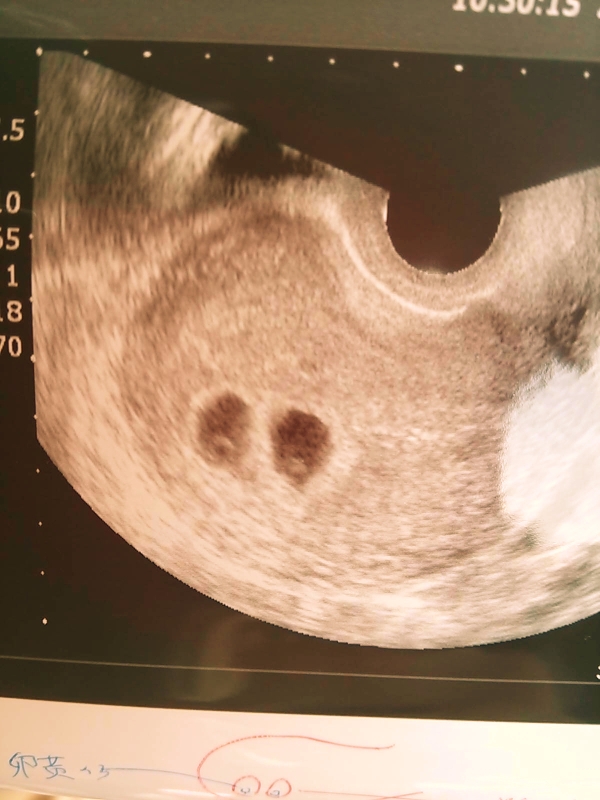

診察台にあがり、エコーを見ながら先生が「3人には増えてないねw」とのこと。

そして、「どうかなー見えるかなー」と言いながら拡大。

双子ともに心臓がぴこぴこしてました。

先生「見えないっていうか、あれ?これ2つあるぞ?ww」

私「2つ?2つって双子ですかー??www」

先生「うん、双子かなぁ。ちょっと待ってよ、他にも隠れてないよねぇwww」

私「三つ子ってことですかwww」

先生「うん、ないね、2つで双子だね、うわぁどうしようかwww双子でも大丈夫?」

私「いや、双子嬉しいですけど、いや、でもうわぁどうしようwww」

先生「どうしようかねwwww」

というわけで、双子でした・・・!!!